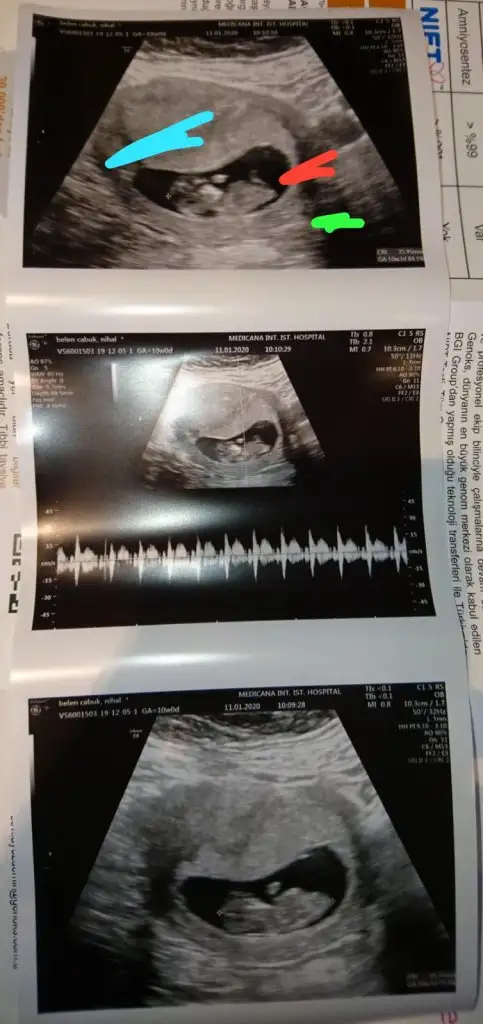

Net degil usg eminde değilim sanki kız varda başka usg paylaşın emin değilim

11 yada 12 hafta varmı

dün gittik 14 hafta usg verdi ama belli olmuyor

Kız bence 9+6 hafta ya göre

Buda kız gibi boş görünüyor bacak arasıdün gittik 14 hafta usg verdi ama belli olmuyor Eki Görüntüle 2575104